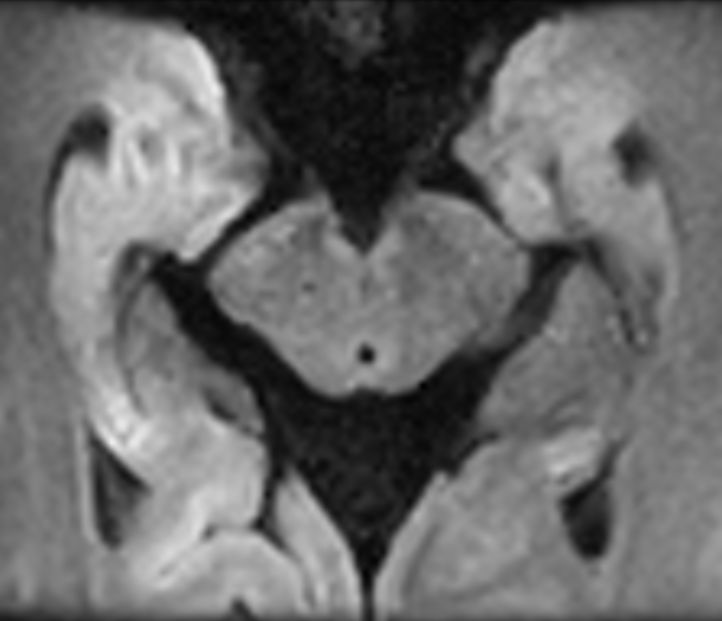

3D VIEW - T1w TSE (coronal reformat)